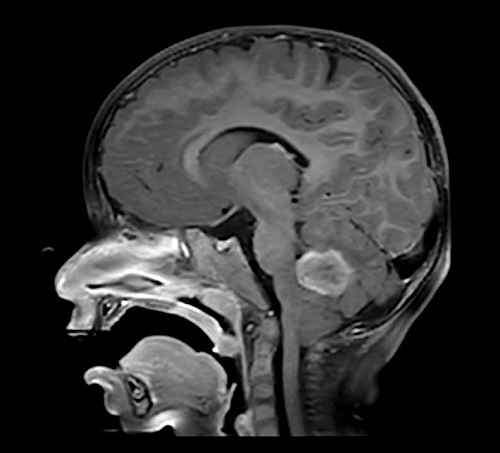

Se realiza una prueba de imagen a los 23 meses de edad, en la que se evidencia una lesión focal intraaxial en la fosa posterior que afecta al cuarto ventrículo, sugestiva de neoformación primaria compatible con ependimoma o glioma de bajo grado (Low Grade Glioma, LGG) (Figura 2, Figura 3 y Figura 4).

Figura 4. Imagen de resonancia magnética en corte frontal donde se visualiza el tumor de fosa posterior. Mostrar/ocultar